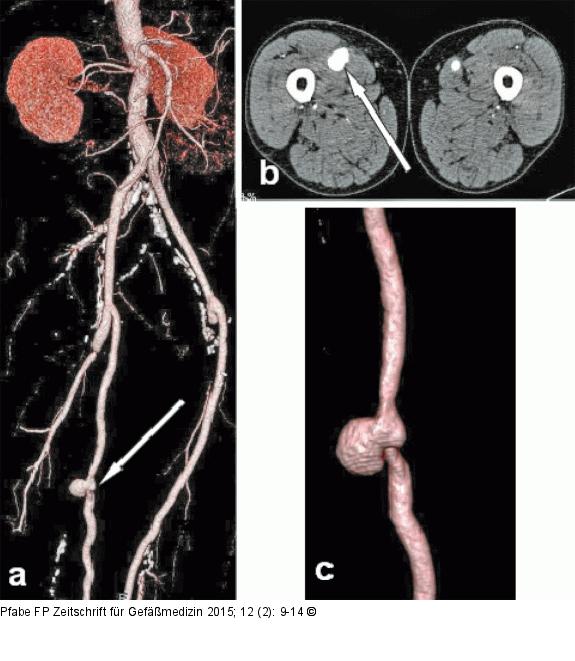

Abbildung 3a-c: CT-Angiographie Kontrastmittelverstärkte CT-Angiographie. (a): Übersicht nach mehrfacher gefäßchirurgischer Rekonstruktion aorto-bipro-fundal und beidseits femoro-popliteal („volume rendering technique“, VRT), anastomosenferne, gedeckte Bypass-Ruptur mit Pseudoaneurysma rechts (Pfeil); (b): kontrastmittelverstärkte CT-Angiographie (Transversal-Schnitt) des pulsierenden Hämatoms rechts (Pfeil); (c): Aneurysma spurium nach semizirkulärer gedeckter Bypass-Ruptur rechts (VRT). |

Kontrastmittelverstärkte CT-Angiographie. (a): Übersicht nach mehrfacher gefäßchirurgischer Rekonstruktion aorto-bipro-fundal und beidseits femoro-popliteal („volume rendering technique“, VRT), anastomosenferne, gedeckte Bypass-Ruptur mit Pseudoaneurysma rechts (Pfeil); (b): kontrastmittelverstärkte CT-Angiographie (Transversal-Schnitt) des pulsierenden Hämatoms rechts (Pfeil); (c): Aneurysma spurium nach semizirkulärer gedeckter Bypass-Ruptur rechts (VRT). |